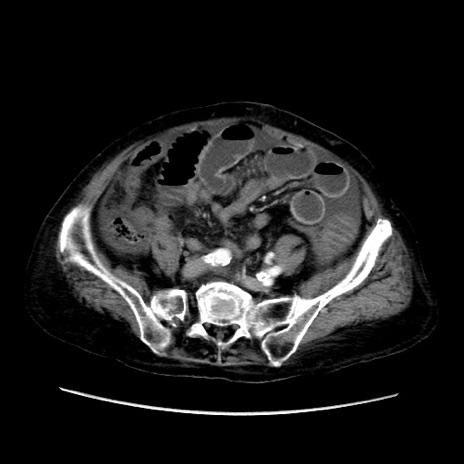

症例31(横断像)

【症例】80歳代 女性

【主訴】腹部膨満感

【現病歴】他院にて肝硬変にてフォロー中。1週間前から便秘、腹部膨満感、臍部腫瘤あり受診となる。

【既往歴】肝硬変

【身体所見】腹部膨隆あり、皮膚変化なし、疼痛なし。

【データ】WBC 4600、CRP 0.25